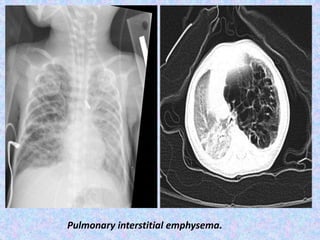

Pulmonary interstitial emphysema.

Pulmonary interstitial emphysema (PIE) refers to the abnormal location of air

within the pulmonary interstitium and lymphatics. It typically results from rupture

of overdistended alveoli following barotrauma in infants who have respiratory

distress syndrome. Interstitial emphysema can also occasionally be incidentally

detected in adults.

CT chest

shows cystic radioculencies in affected segment may characteristically show a line

and dot pattern with pulmonary arterial branches surrounded by radiolucent air

may help differentiate persistent PIE from a hyperlucent mass such as congenital

lobar emphysema, congenital pulmonary airway malformation (CPAM)

allows better visualization of a pneumothorax or pneumomediastinum

if incidentally detected in adults, it may appear as perivascular lucent or low-

attenuating halos and small cysts.